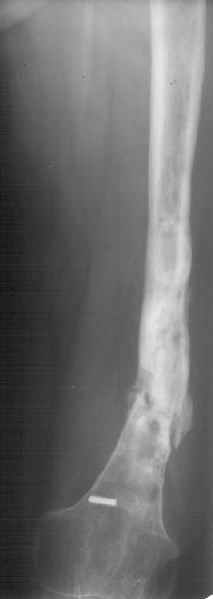

К нам поступила худощавая женщина 48 лет, которой года 2,5 назад был выполнен остеосинтез бедра пластинкой в одной из горбольниц. В сентябре 2001 г. пластинку убрали. Начала разрабатывать движения, ходила с тростью. С января этого года

отмечает усугубление деформации бедра и улучшение движений "в коленном суставе". При осмотре имеетсяподвижность на месте перелома (псевдартроза), больше в сагиттальной плоскости. Рентгенограммы в приложении(фас; профиль). Полностью угол, открытый кзади, под нагрузкой не устраняется. "Сгибается" еще градусов на 30. Ходит с тростью. Надколенник неподвижен, в суставе, видимо, движений нет совсем. В любом случае надо, видимо, начинать с восстановления оси и стабилизации бедра. Как окончательный фиксатор хотелось бы использовать интрамедуллярный стержень. Можно ли в данном случае устранить угол одномоментно? Или лучше дозированно? Нужна ли костная пластика местно? Не стоит ли пойти на мобилизующую операцию в один этап? Если да, то какую?Может быть, есть еще какие-то моменты, которые следует учесть?Спасибо заранее.-- Best regards, Alexander N. Chelnokov

Клинико-рентгенологически - замедленная консолидация.

Если инфекция присутствует (вполне возможно, судя по рентгенограмме), резекция инфицированной, некротизированной кости, замещение образовавшегося дефекта с помощью транспорта костного блока в аппарате.